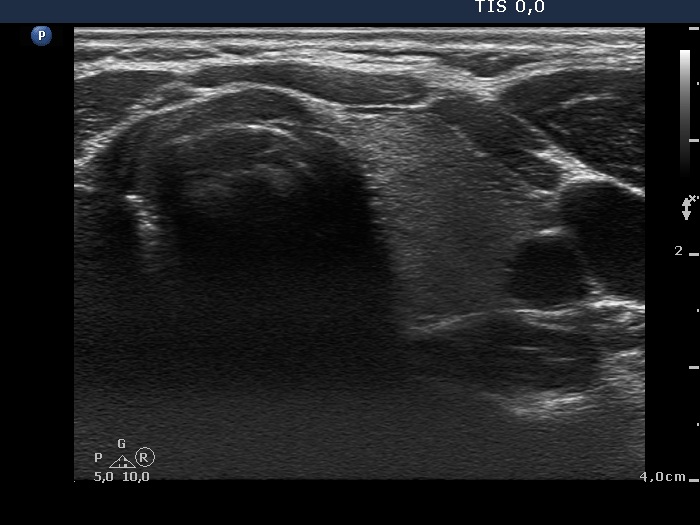

Benign nodular hyperplasia - Case 53. (ultrasonographic picture 7)

Left lobe, horizontal scan. This lobe is intact.